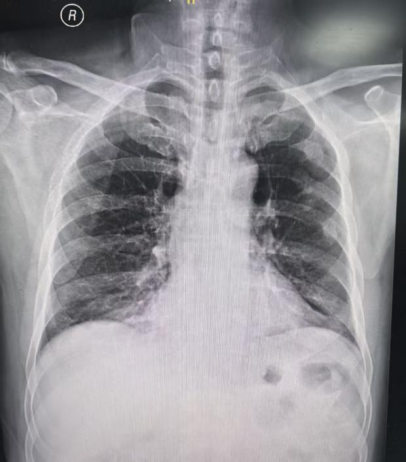

辅助检查(11月10日):

胸部CT:双肺炎症。

11月10日: